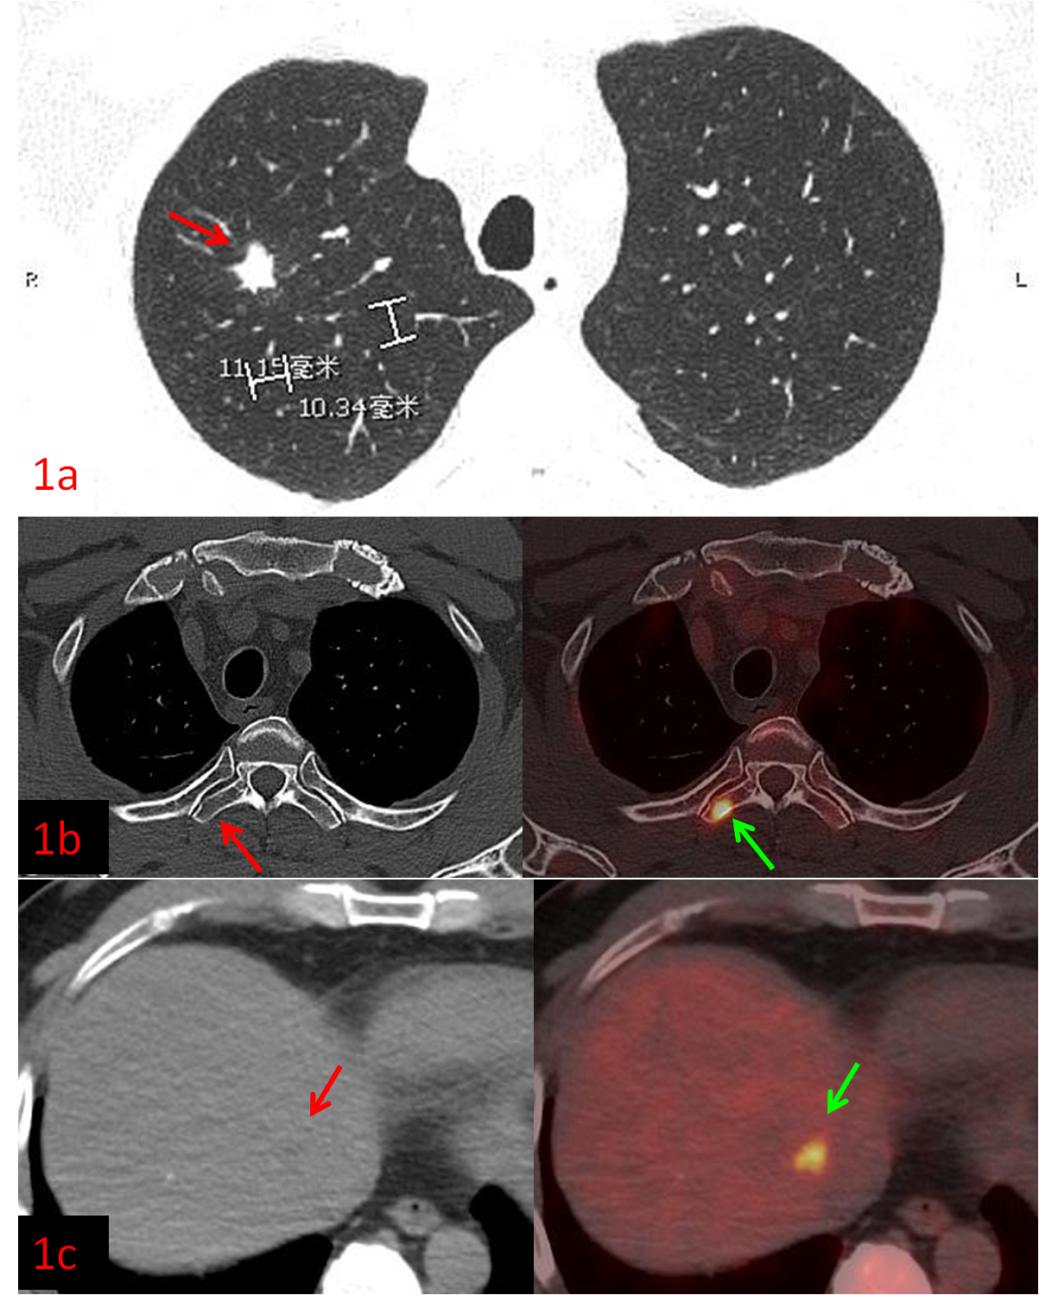

例1:中年男性,CT發(fā)現右肺上葉結節(jié),1.1cm×1.0cm,余未見異常,這時候患者初步分期應該是ⅠA期,屬于早期肺癌,可以行根治性手術。而PET/CT檢查示:肝臟、多發(fā)骨骼轉移,這時候分期直接跳到ⅣB期,屬于晚期肺癌,不適合手術,可以根據病理、基因檢測結果選擇合適的藥物治療或聯(lián)合治療方案,避免了無效的手術創(chuàng)傷。病理:浸潤性腺癌。